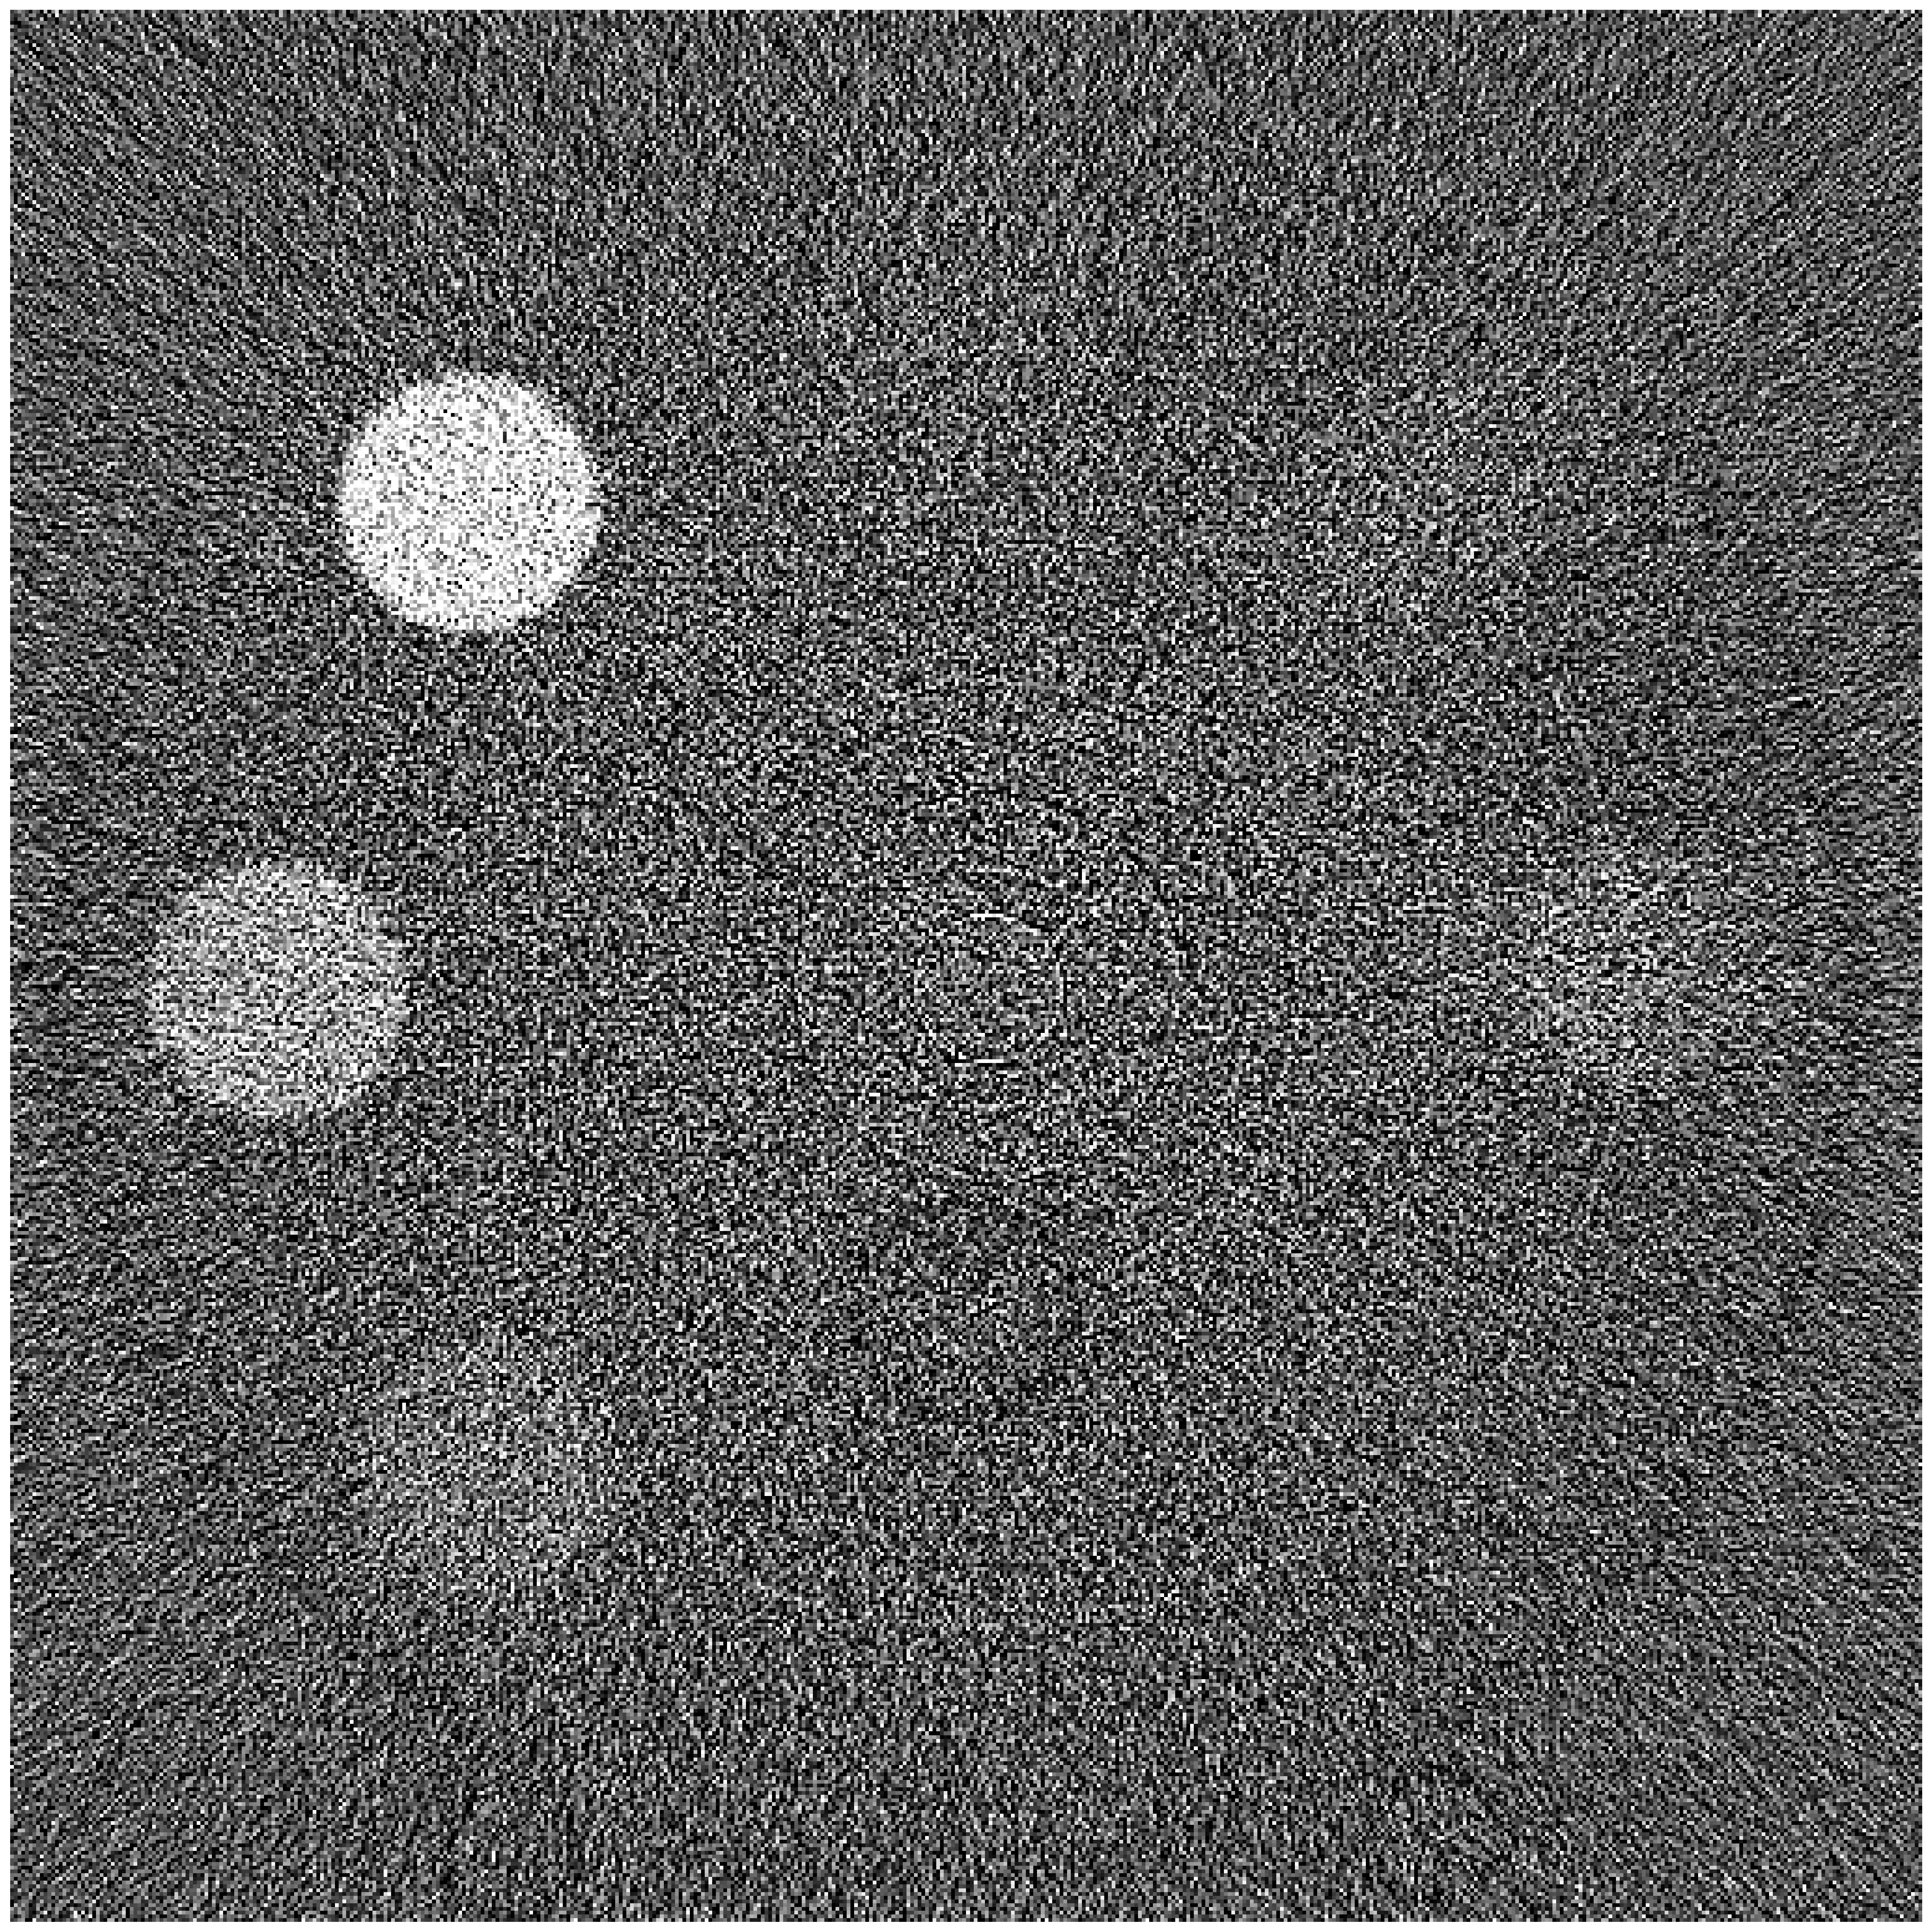

The left and right panels of Figure 2 show the baseline MLE and proposed algorithm reconstructions of the simulated data, respectively. The reconstruction is shown in Hounsfield units (HU), modified so that air is 0 and water is 1000, with a center of 1000 HU and a window width of 20 HU. The result using our proposed method uses a simple linear filter as a prior but is still able to distinguish inserts with less than deviation from water density, even for very small feature lengths.